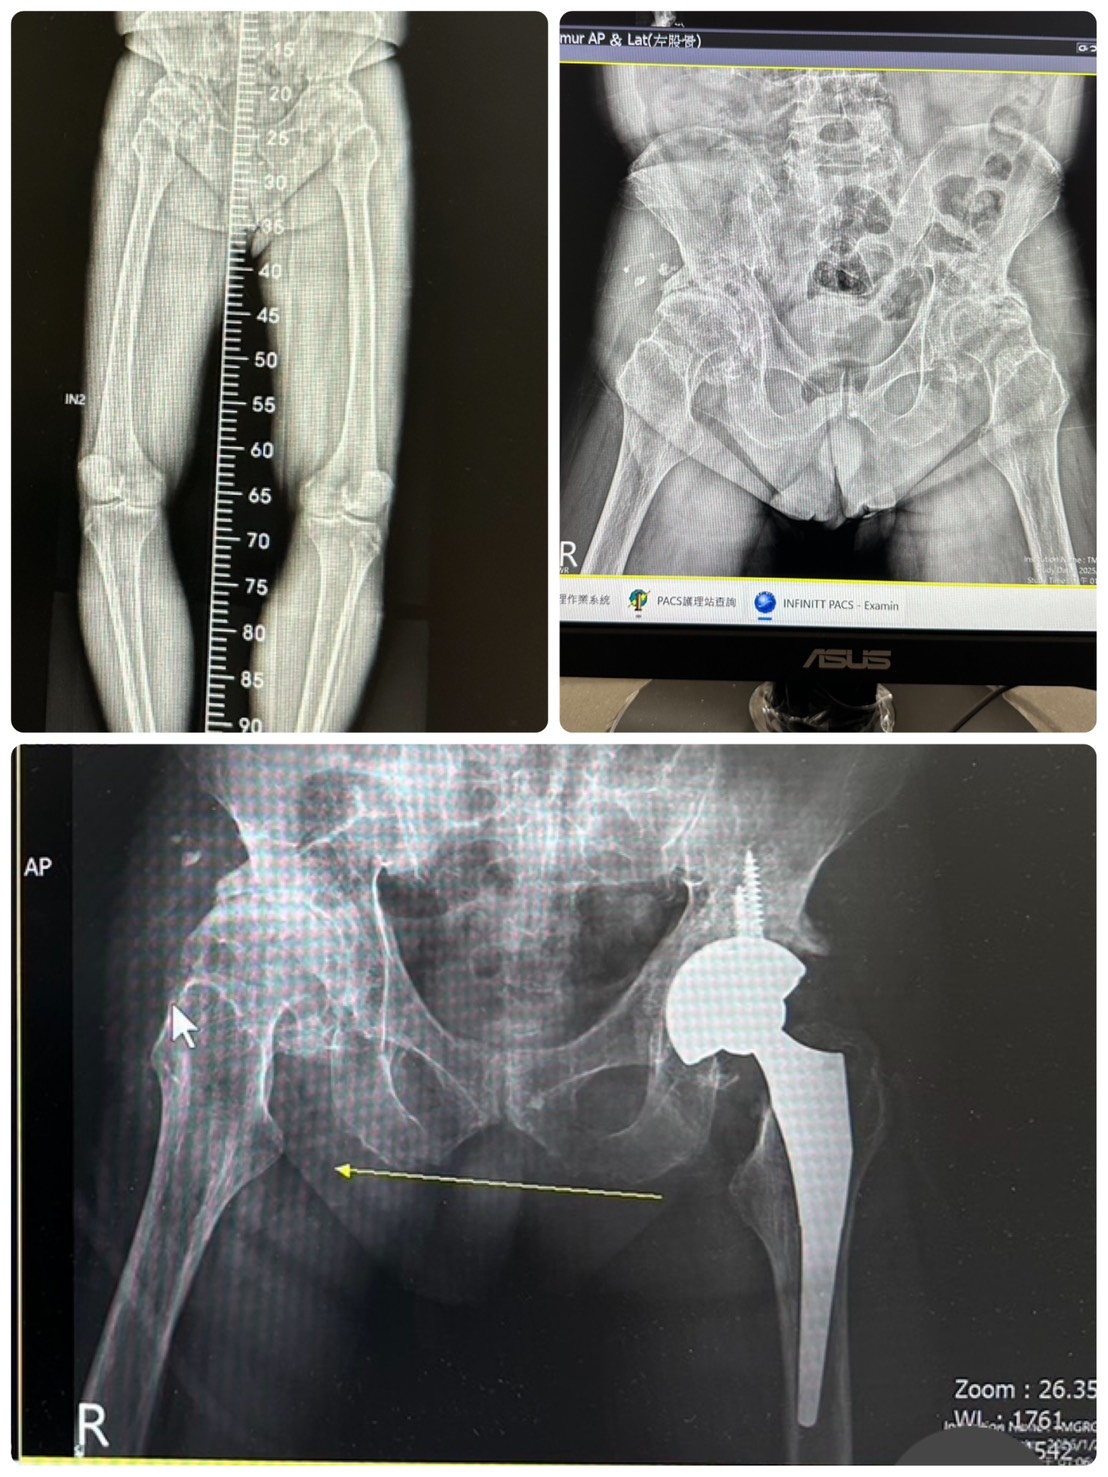

Q: Will the surgery cause "leg length discrepancy"?

Physician's Answer: This was indeed a risk with traditional surgery. However, minimally invasive surgery, combined with surgeon skill and technique, can minimize this difference. Sometimes, to ensure optimal joint tension based on the patient's specific condition, minor adjustments may still be necessary.